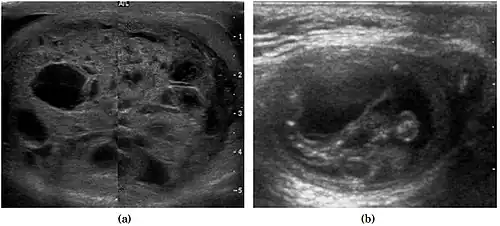

At ultrasound, tuberculous epididymitis is characterized by an enlarged epididymis with variable echogenicity. The presence of calcification, caseation necrosis, granulomas and fibrosis can result in heterogeneous echogenicity [Fig. 21a]. The ultrasound findings of tuberculous orchitis are as follow: (a) diffusely enlarged heterogeneously hypoechoic testis (b) diffusely enlarged homogeneously hypoechoic testis (c) nodular enlarged heterogeneously hypoechoic testis and (d) presence of multiple small hypoechoic nodules in an enlarged testis [Fig. 21b].

Although both bacterial and tuberculous infections may involve both the epididymis and the testes, an enlarged epididymis with heterogeneously hypoechoic pattern favors a diagnosis of tuberculosis (Muttarak and Peh, 2006, as cited in Kim et al., 1993 and Chung et al., 1997). With color Doppler ultrasound, a diffuse increased blood flow pattern is seen in bacterial epididymitis, whereas focal linear or spotty blood flow signals are seen in the peripheral zone of the affected epididymis in patients with tuberculosis.